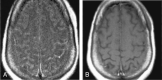

F<sc>ig</sc> 5.

Fig 5.

Patient with meningeal involvement. A, Axial contrast-enhanced FLAIR image shows increased signal intensity in the sulci compatible with meningitis. B, Abnormality is not appreciated on the corresponding contrast-enhanced T1WI.